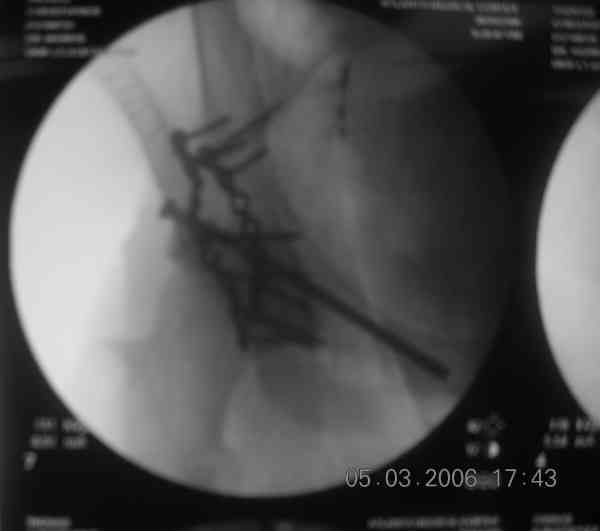

the case that I found is a 20yo male, MCC. his AP pelvis shows an interesting position of his bladder. it is pushed aside by a hematoma from SGA injury. we did a limited lateral window approach for the anterior column first, pt bumped up/supine. then closed and repositioned for KL. I could not find intra-op photos of cases when we did only a small incision for the AC screw (but they do exist!!). the lateral window is available for reduction assessment if a KL approach is being used. in the lateral position this window is available. the prone position definitely takes pressure off of the post column and facilitates reduction. in the lateral position a schantz pin in the ischial tub +/- bone hook in sciatic notch helps with PC reduction. the lateral position also gives better airway access for anesthesia. airway problems are rare, but prone position seems to be a bit more of a challenge to exchange the tube, or reintubate altogether. just something further to debate!